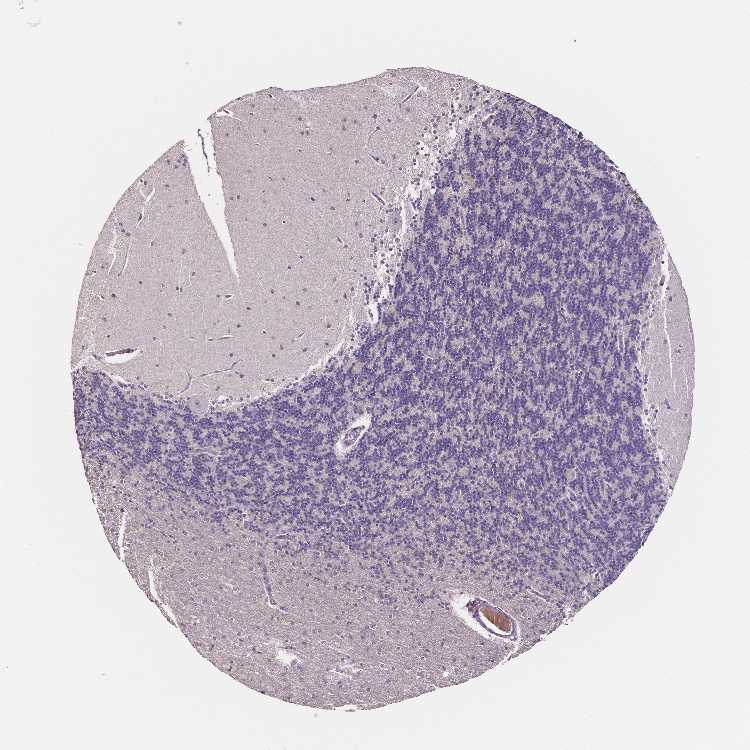

BRAIN CEREBELLUM Show tissue menu

CEREBELLUM - Expression summary

CEREBELLUM - Antibody stainingi

Antibody staining in the annotated cell types in the current human tissue is reported as not detected, low, medium, or high, based on conventional immunohistochemistry profiling in selected tissues. This score is based on the combination of the staining intensity and fraction of stained cells.

Each image is clickable and will lead to virtual microscopy that enables deeper exploration of all samples and also displays staining intensity scores, fraction scores and subcellular localization as well as patient and tissue information for each sample.

Antibody HPA038171Antibody CAB006908

Purkinje cells Not detectedNot detected

Cells in granular layer Not detectedNot detected

Cells in molecular layer Not detectedNot detected